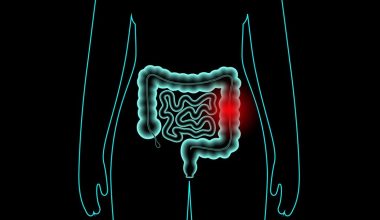

Το αυχενικό σύνδρομο είναι πολύ συχνή πάθηση που επιδεινώνεται με την ηλικία. Πάνω από το 85% των ατόμων ηλικίας άνω των 60 ετών ταλαιπωρείται σε κάποιο βαθμό από προβλήματα στον αυχένα.

Καθώς οι δίσκοι στους σπονδύλους αφυδατώνονται και συρρικνώνονται, εκδηλώνονται συμπτώματα οστεοαρθρίτιδας, συμπεριλαμβανομένων των οστικών προεξοχών κατά μήκος των άκρων των οστών.

Αυχενικό σύνδρομο: Αιτίες εμφάνισης και επιδείνωσης του πόνου στον αυχένα

Καθώς μεγαλώνετε, τα οστά και οι χόνδροι που συνθέτουν σπονδυλική στήλη και τον αυχένα σας να αναπτυχθεί, αρχίζουν και φθείρονται σταδιακά. Αυτή η φθορά επιφέρει ορισμένες αλλαγές, όπως:

- Αφυδατωμένοι δίσκοι: Οι μεσοσπονδύλιοι δίσκοι λειτουργούν σαν “μαξιλαράκια” ανάμεσα στους σπονδύλους της σπονδυλικής σας στήλης. Περίπου από την ηλικία των 40 ετών και μετά, οι δίσκοι αυτοί αρχίζουν να αφυδατώνονται και να συρρικνώνονται. Αυτό, σταδιακά επιτρέπει περισσότερη άμεση επαφή (και άρα φθορά) οστό-με-οστό μεταξύ των σπονδύλων.

- Δισκοκήλη: Η ηλικία επηρεάζει επίσης το εξωτερικό περίβλημα των μεσοσπονδύλιων δίσκων. Αρχίζουν να εμφανίζονται ρωγμές, κάτι που οδηγεί σε διόγκωση (κήλη) του δίσκου. Αυτή η διόγκωση οδηγεί πολλές φορές σε πίεση στα νεύρα της σπονδυλικής στήλης και ως εκ τούτου σε πόνους που εκτείνονται μέχρι το χέρι ή το πόδι.

- Οστικά εξογκώματα: Η εκφύλιση του δίσκου οδηγεί συχνά στην αύξηση των οστών της σπονδυλικής στήλης σε μια προσπάθεια του οργανισμού να εξισορροπήσει το πρόβλημα, ενισχύοντας περισσότερο τα οστά της σπονδυλικής στήλης. Αυτό δημιουργεί οστικά εξογκώματα στους σπονδύλους, τα οποία μερικές φορές ασκούν πίεση στα τοπικά νεύρα.

- Δύσκαμπτοι σύνδεσμοι: Οι σύνδεσμοι είναι σας “κορδόνια” ιστού που συνδέονται με τα οστά. Οι σπονδυλικοί αυτοί σύνδεσμοι σκληραίνουν με την ηλικία, καθιστώντας τον αυχένα σας λιγότερο εύκαμπτο.